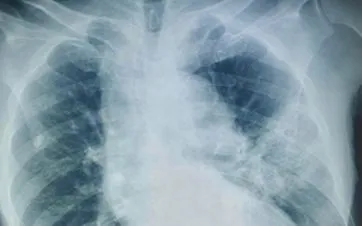

Trong quá trình điều trị, bệnh nhân diễn tiến nặng nhanh với suy hô hấp, sốt dao động 39-40 độ C và đáp ứng kém với phác đồ kháng sinh phổ rộng (piperacillin/tazobactam phối hợp levofloxacin). Trước tình trạng lâm sàng không cải thiện, bệnh nhân được nội soi phế quản. Kết quả cấy dịch rửa phế quản sau 5 ngày nhập viện cho thấy Candida albicans.

Candida albicans là nấm men thường trú ở niêm mạc miệng - hầu họng, thường không gây bệnh khi cơ thể khỏe mạnh. Tuy nhiên, ở người cao tuổi, suy giảm miễn dịch hoặc sử dụng kháng sinh phổ rộng kéo dài, nấm có thể gây nhiễm trùng xâm lấn, trong đó viêm phổi là thể bệnh khó chẩn đoán do biểu hiện lâm sàng và hình ảnh học không đặc hiệu.

Chẩn đoán xác định nhiễm Candida xâm lấn cần dựa vào cấy nấm dương tính từ các bệnh phẩm vô khuẩn hoặc mô bệnh học. Trên lâm sàng, cần nghĩ đến căn nguyên nấm khi bệnh nhân viêm phổi nặng, sốt kéo dài, không đáp ứng kháng sinh sau 4-7 ngày, đặc biệt ở nhóm nguy cơ cao.